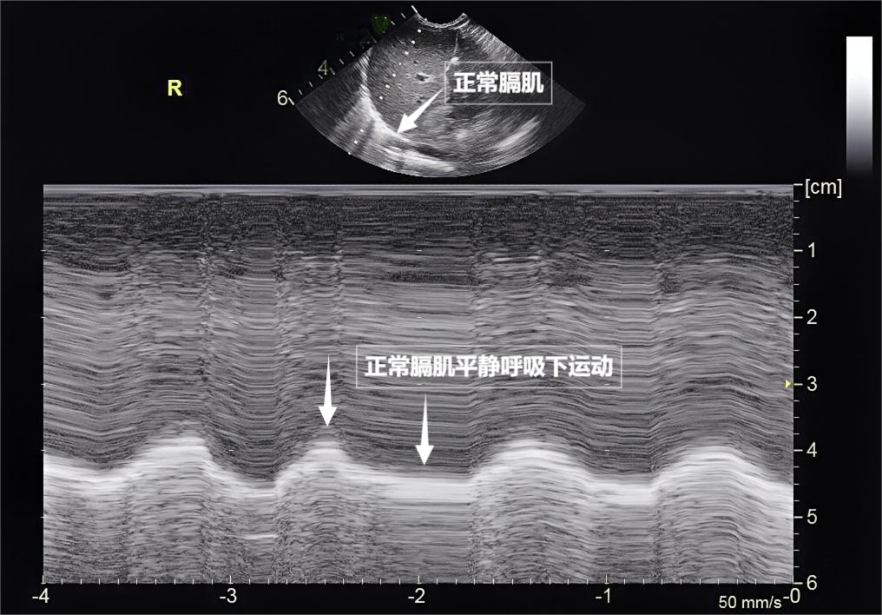

第三景:“呼吸的動力泵”的協(xié)同作戰(zhàn)——呼吸肌肉

呼吸看似簡單,實則是多組肌肉精密配合的“團體操”。肺部超聲不僅能觀察肺的形態(tài),更能通過實時動態(tài)影像,“捕捉”這些呼吸肌的活動狀態(tài),為評估呼吸功能提供獨特視角。膈肌是呼吸肌的“總指揮”,位于胸腔與腹腔之間。平靜呼吸時,膈肌收縮下沉,胸腔容積擴大,空氣自然吸入;舒張時,膈肌回升,肺部彈性回縮完成呼氣。超聲下可見膈肌呈光滑弧形,隨呼吸規(guī)律上下移動(見下圖)。肋間外肌則是“肋間隙的升降機”,收縮時上提肋骨,擴大胸腔前后徑,輔助吸氣。這對“黃金搭檔”承擔了日常呼吸70%以上的工作量,是維持呼吸的“主力軍”。

圖為正常膈肌超聲表現(xiàn)